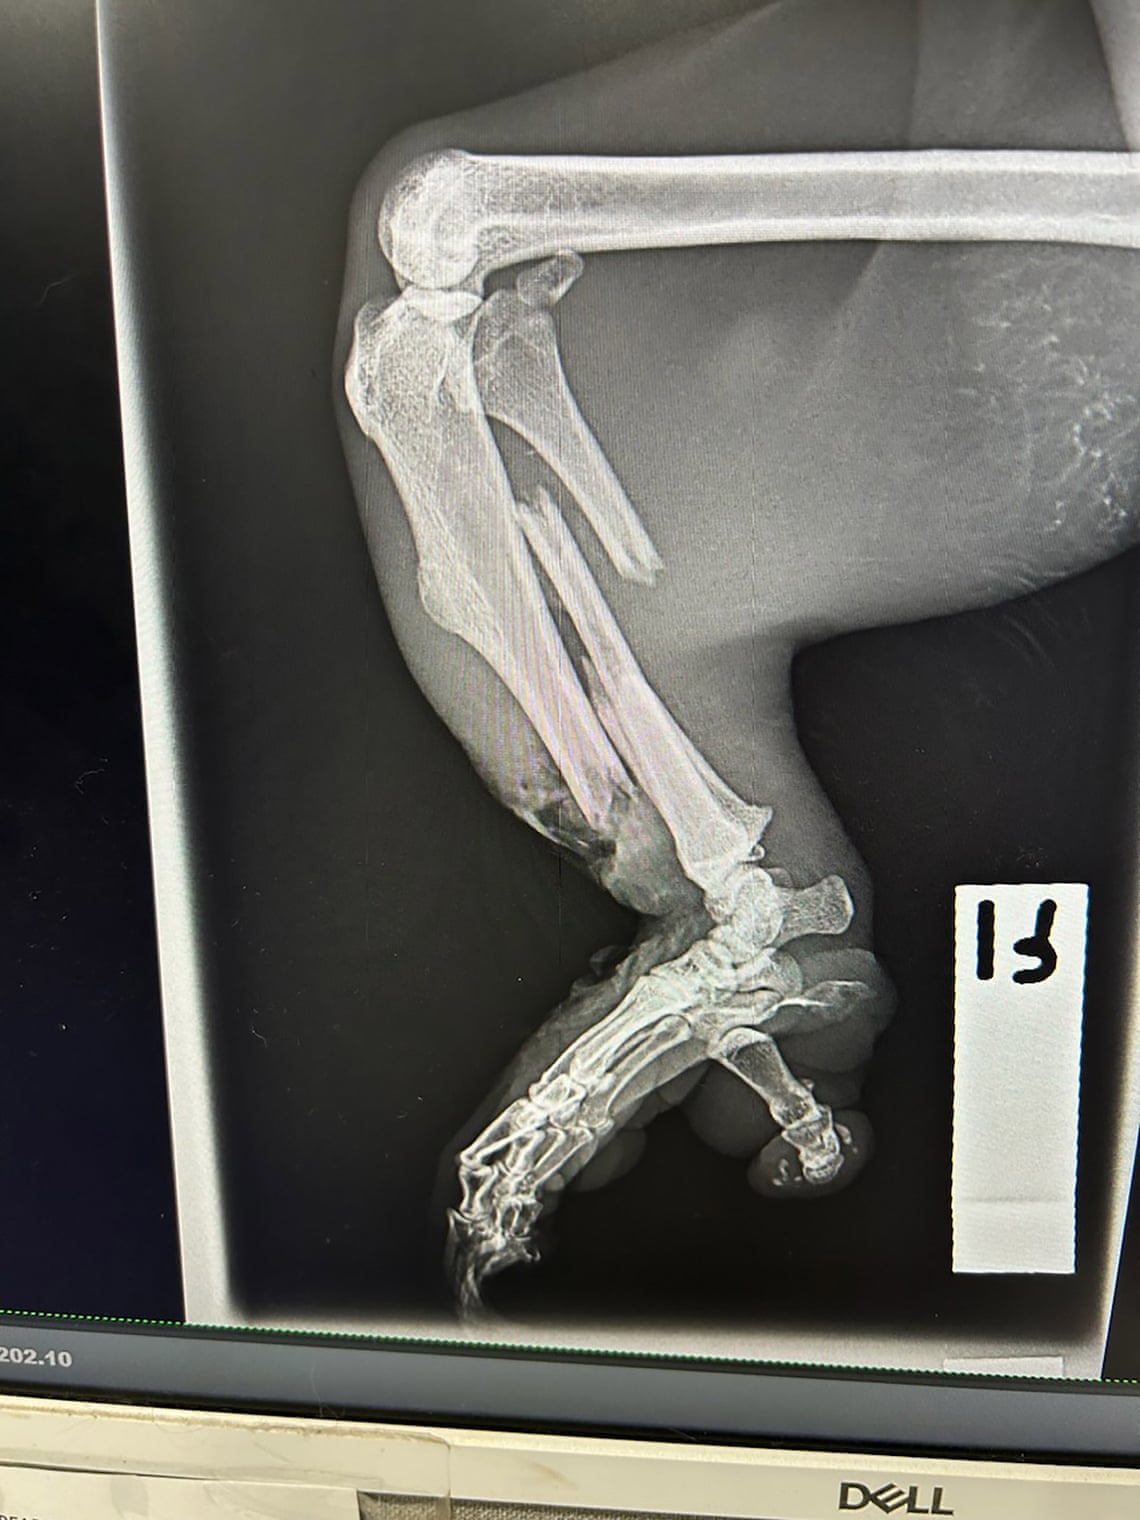

Guardian Australia obtuvo fotografías que muestran koalas gravemente heridos y fallecidos en el lugar. Los ex empleados afirmaron haber intentado salvar al menos 40 koalas heridos, mientras que alrededor de 20 murieron durante la actividad de tala destinada a la agricultura.